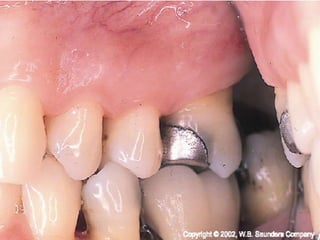

The partially erupted or impacted

mandibular third molar is the most

common site of pericoronitis.

The space between the

crown of the tooth &

overlying gingival flap is an

ideal area for the

accumulation of food

debris & bacterial growth.